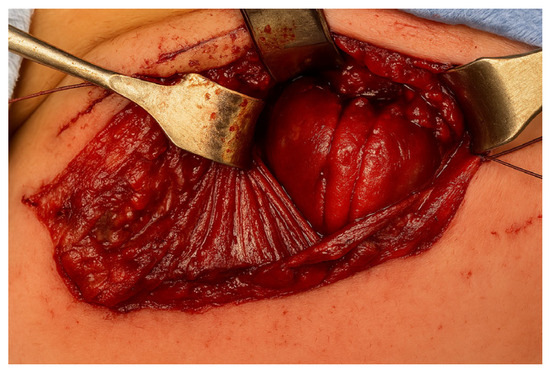

A right-sided cervicotomy was performed, through which both the proximal and distal esophageal pouches were identified very close together. Therefore, a primary end-to-end anastomosis was successfully performed without tension using interrupted absorbable sutures (Figure 4).

Figure 3. Anatomical point of view: both esophageal pouches located in the cervical region, allowing primary anastomosis via a cervical approach.

Figure 4. The end-to-end esophageal anastomosis by cervical approach.